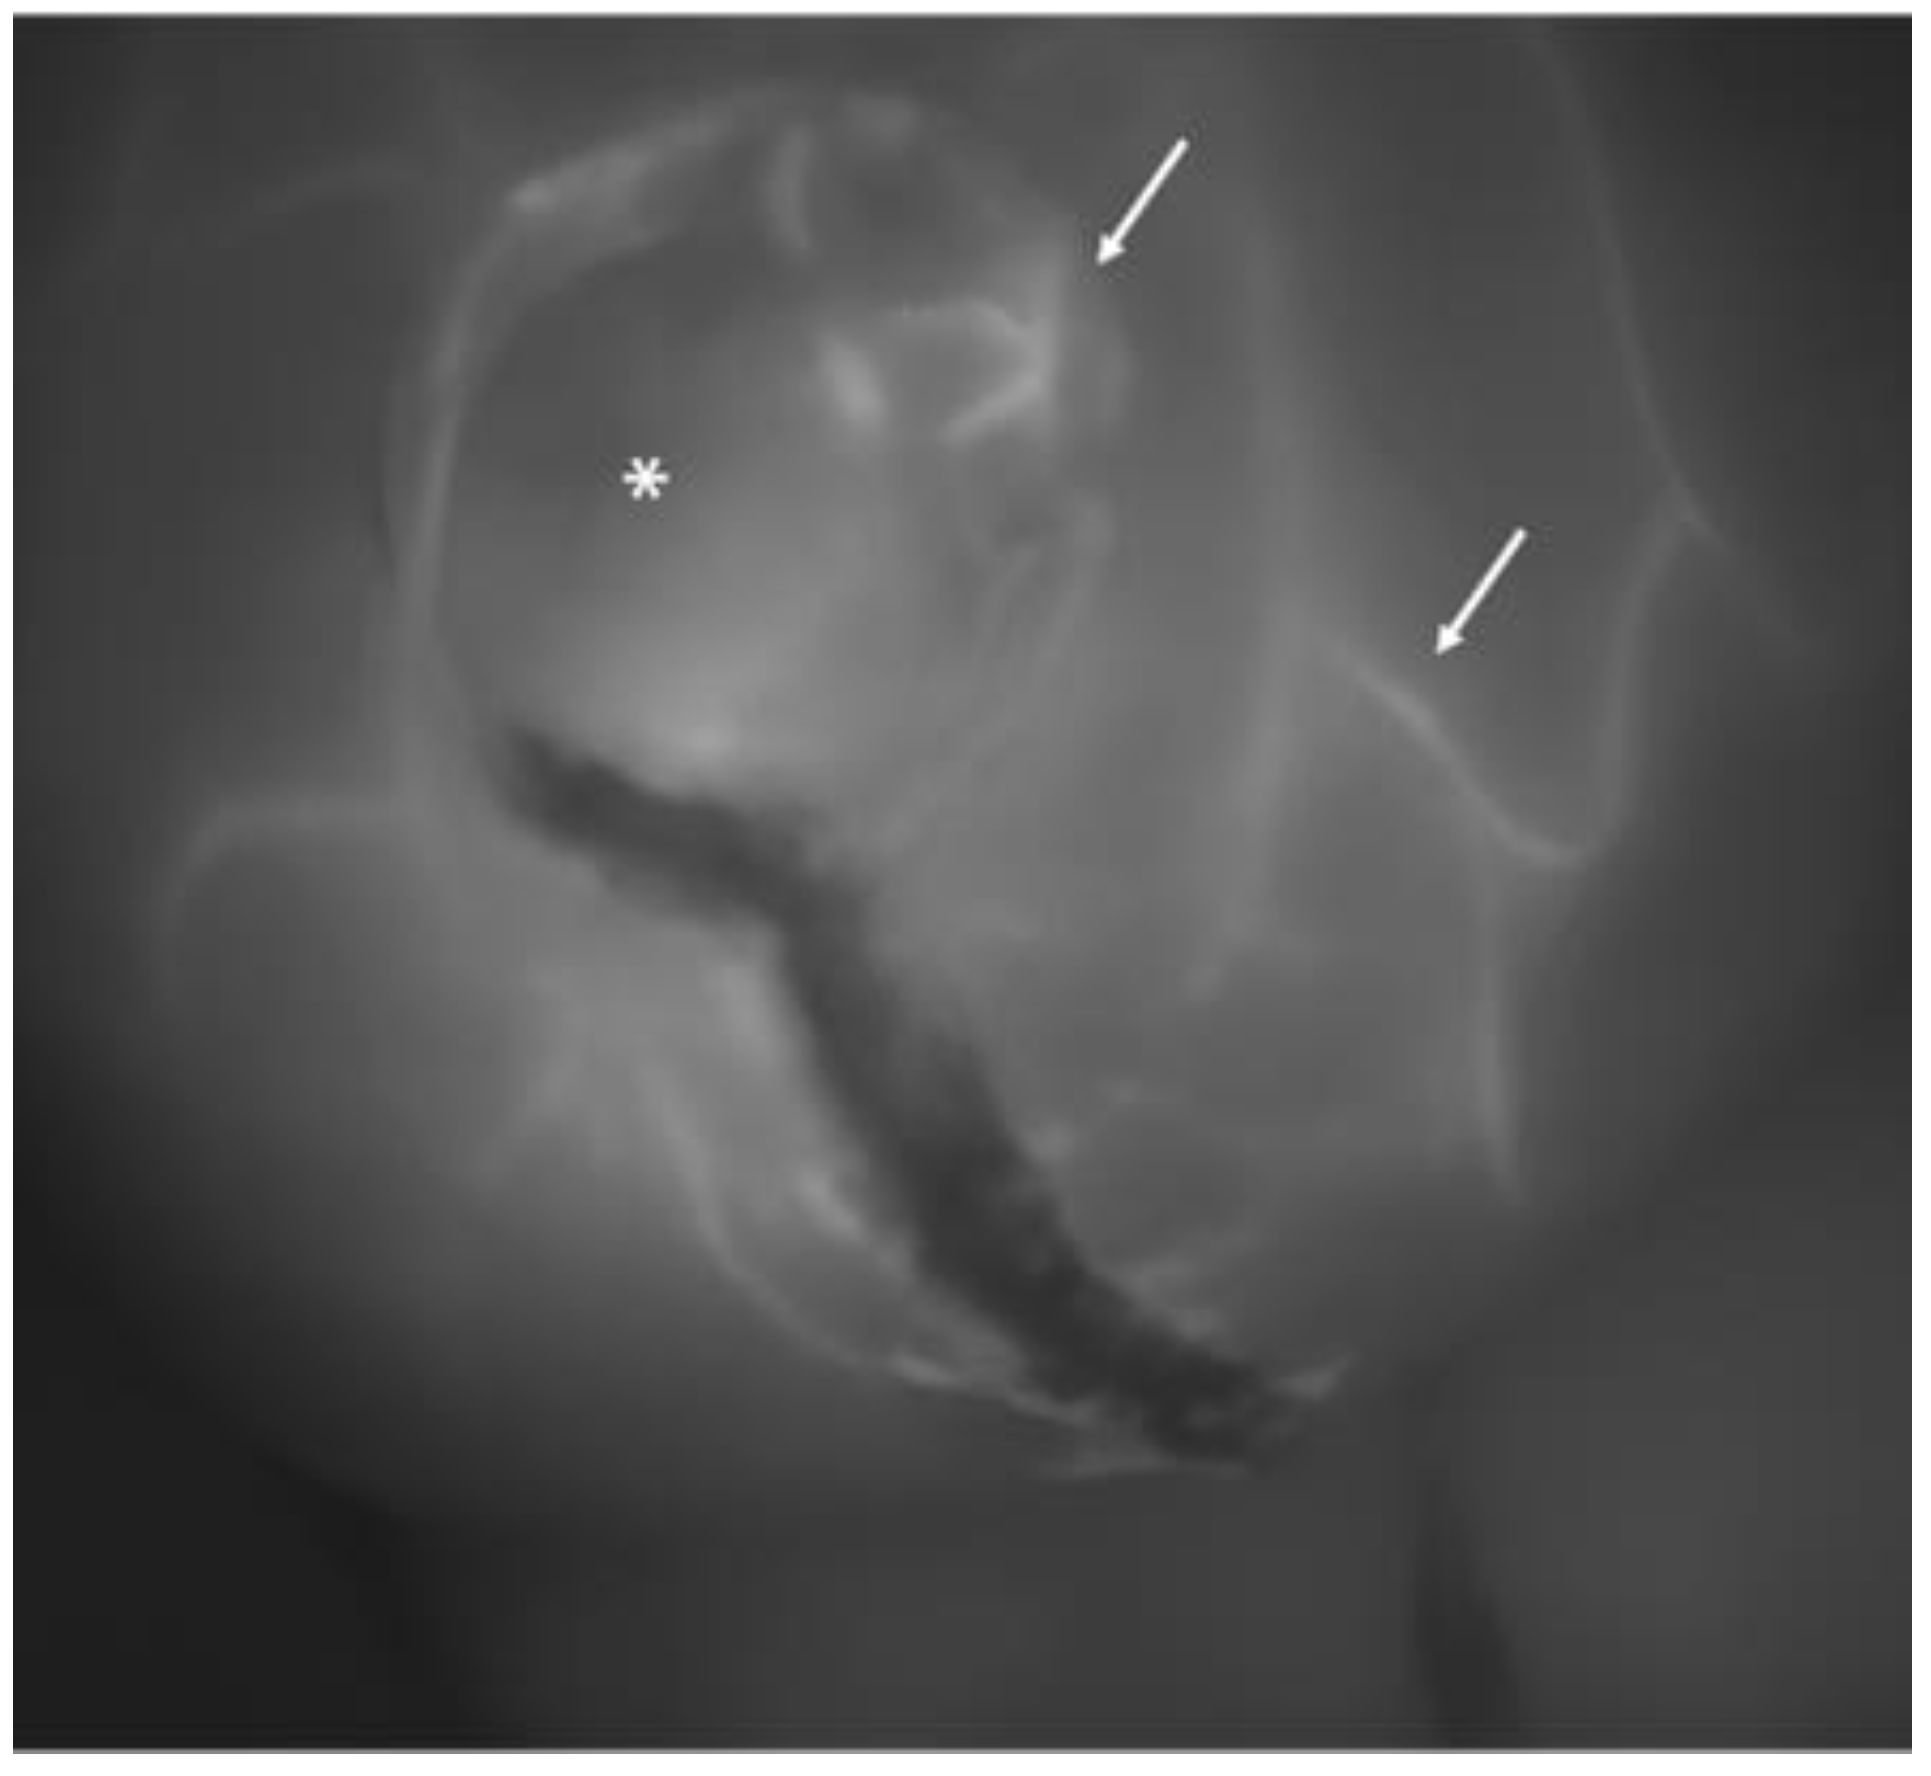

Figure 2.

Another image of a breast at the completion of the procedure: the asterisk indicates a skin perforator vessel from which several small tangential vessels branch out (white arrows). This pattern is characteristic of a well-perfused skin flap.